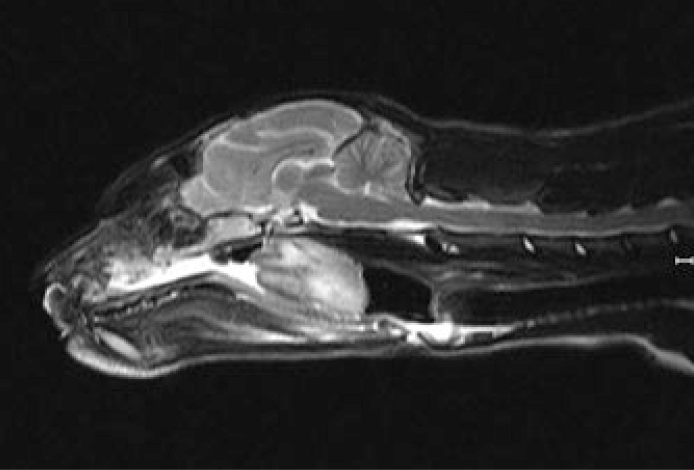

Все о том как делают МРТ собаке

Услуги по проведению МРТ собаке предоставляют только несколько специализированных ветеринарных клиник города Санкт-Петербург. Спрос на такую диагностику растет с каждым днем. Наши домашние питомцы точно так же, как и мы, подвержены заболеваниям головного и спинного мозга, внутренних органов, позвоночника и суставов. Они могут получать травмы опорно-двигательного аппарата, что иногда требует срочного хирургического вмешательства. Чтобы установить точный диагноз, обычного визуального обследования у ветеринара порой бывает недостаточно, поэтому приходится прибегать к аппаратным методам диагностики - магнитно-резонансной томографии, компьютерной томографии, УЗИ и рентгену.

Чаще всего проведение МРТ собаке требует использования контрастного вещества. Оно представляет собой препарат, синтезированный из соли гадолиния. Он увеличивает тканевую контрастность снимков и повышает четкость и яркость томографических изображений.

В результате МРТ ветеринарный врач-диагност получает снимки обследуемой области. На их основании становятся ясными шансы на излечение животного и разрабатывается курс медикаментозного лечения или операционного вмешательства.